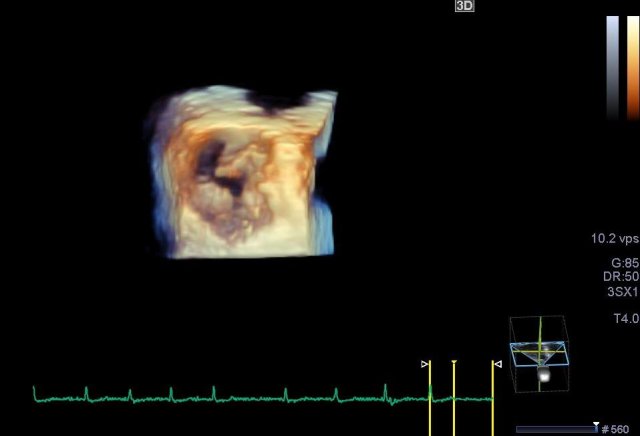

Herzspitzenaneurysma in 3D